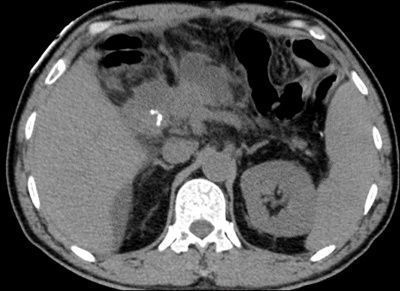

ct增强:十二指肠降段肠壁局部不规则结节样增厚,凸向腔内,中度强化.